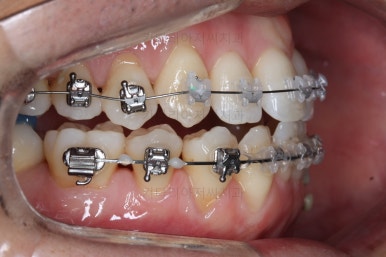

부산비수술교정 키다리아저씨치과에서 시행한 이번 치료의 결과입니다.

옆모습이 주걱턱 느낌이 많이 없어졌고 볼록하던 아랫입술도 뒤로 들어갔어요. 앞니가 거꾸로 물리지 않게 되어 웃거나 말하는 모습도 자연스러워졌어요.

아랫니 갯수가 모자라고 중앙이 맞지 않았고 짝이 안맞는 상황이었으나 비교적 잘 마무리를 했어요.

거꾸로 물리는 상황이 개선되었기 때문에 앞니나 어금니의 교합은 이전과 비교할 수 없을만큼 좋아졌지요.